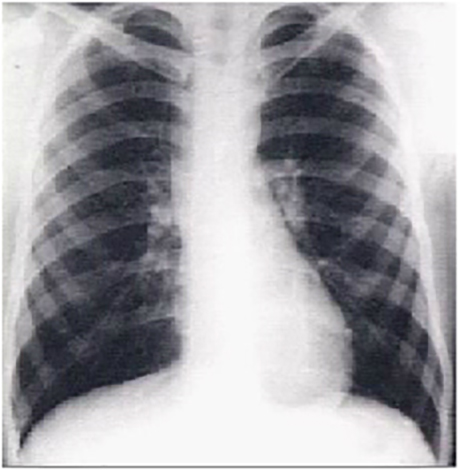

You are incorrect - the best interpretation of the chest X rays in our patient is that they are normal.

These chest X rays show a dilated ascending aorta.

The PA view demonstrates dilatation of the ascending portion of the aorta as evidenced by a prominent bulge in the right mediastinal shadow. Note that the heart size is normal, as reflected by a cardiothoracic ratio less than 50%.